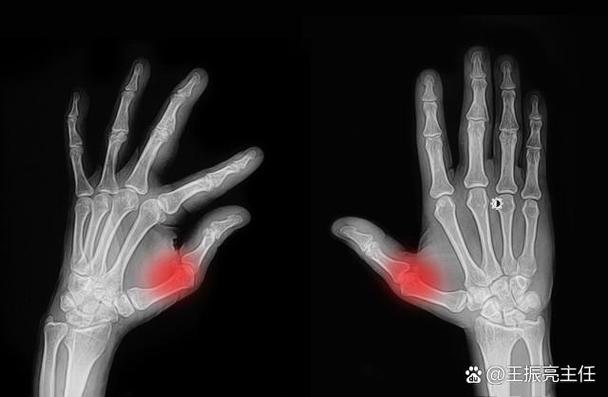

- 体格检查:检查关节是否有红、肿、热、痛和活动受限。

- 影像学检查:X光、超声波或MRI,用于观察关节损伤情况。